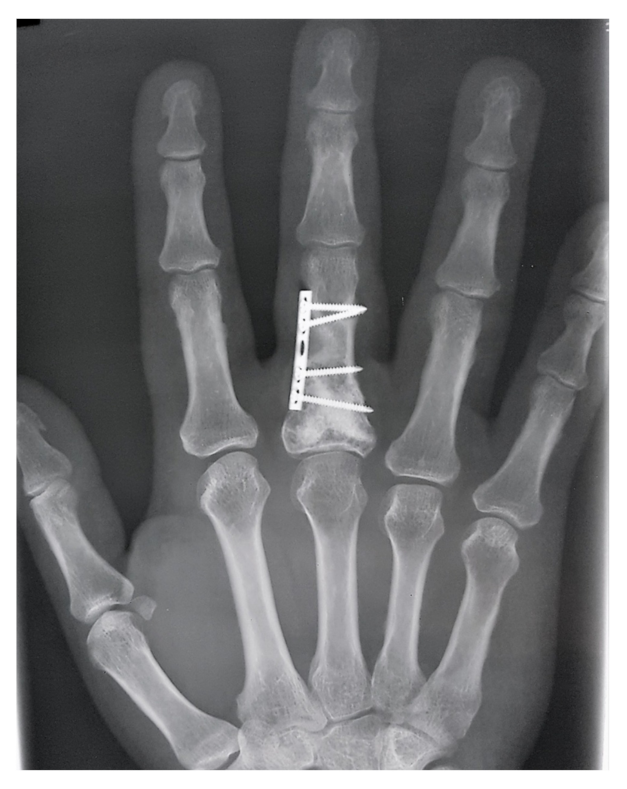

Enchondroma Hand

Enchondroma - Azouz Hand SurgeryAzouz Hand Surgery Enchondromas - Pathology - Orthobullets LearningRadiology- Enchondroma Enchondroma-of-hand LearningRadiology- Enchondroma Enchondroma Hand